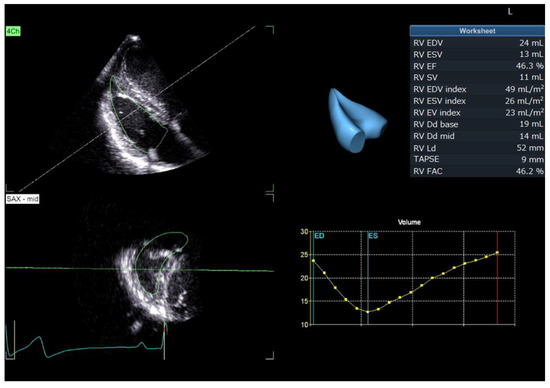

2.5. RT3DE